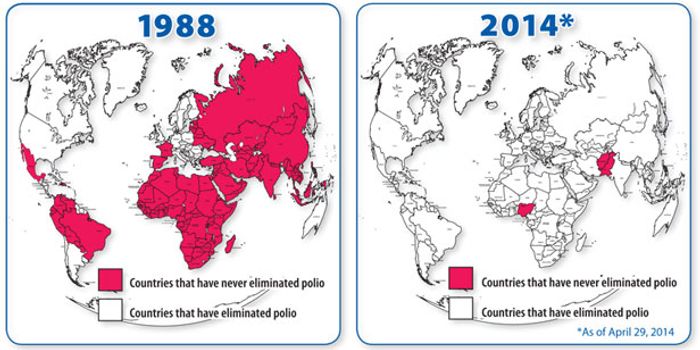

AUG 29, 2017InfographicsOver the years, vaccines have prevented countless cases of disease and saved millions of lives. Currently, there are ove ...

JAN 02, 2016ImmunologyPolio is close to being eradicated, and once it is, scientists want to keep it that way. The live attenuated polio vacci ...